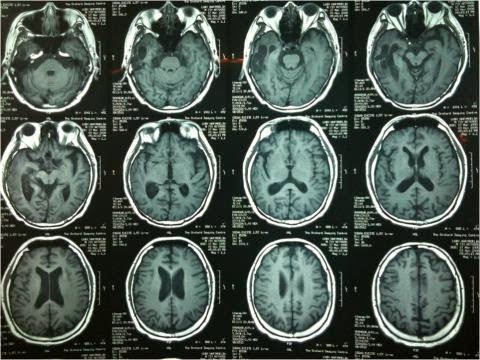

· MRI

Untuk

mengetahui adanya edema, infark hematom dan bergesernya struktur otak